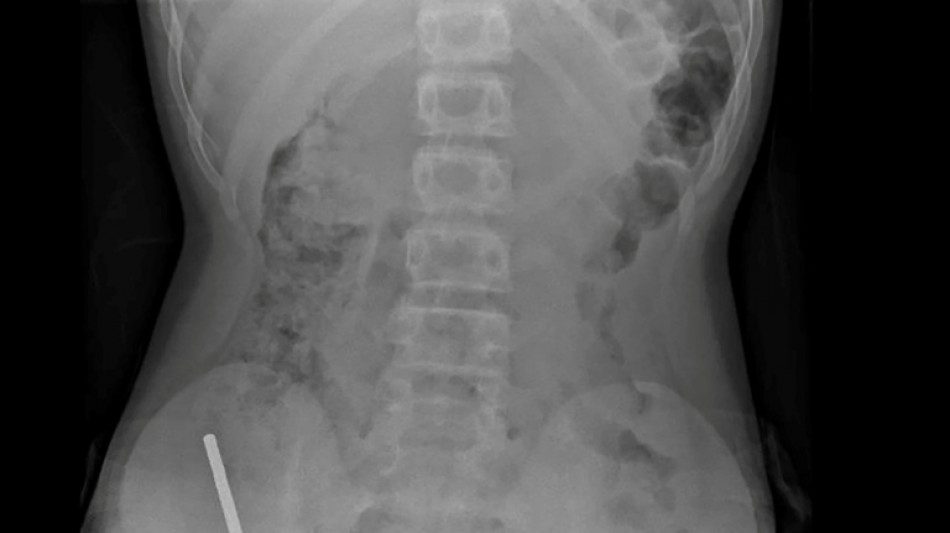

Surgeons remove up to 100 magnets from N. Zealand teen's gut / Photo: Handout - NEW ZEALAND MEDICAL JOURNAL (NZMDJ)/AFP

An X-ray showed the magnets had clumped together in four straight lines inside the child's intestines.

"These appeared to be in separate parts of bowel adhered together due to magnetic forces," they said.